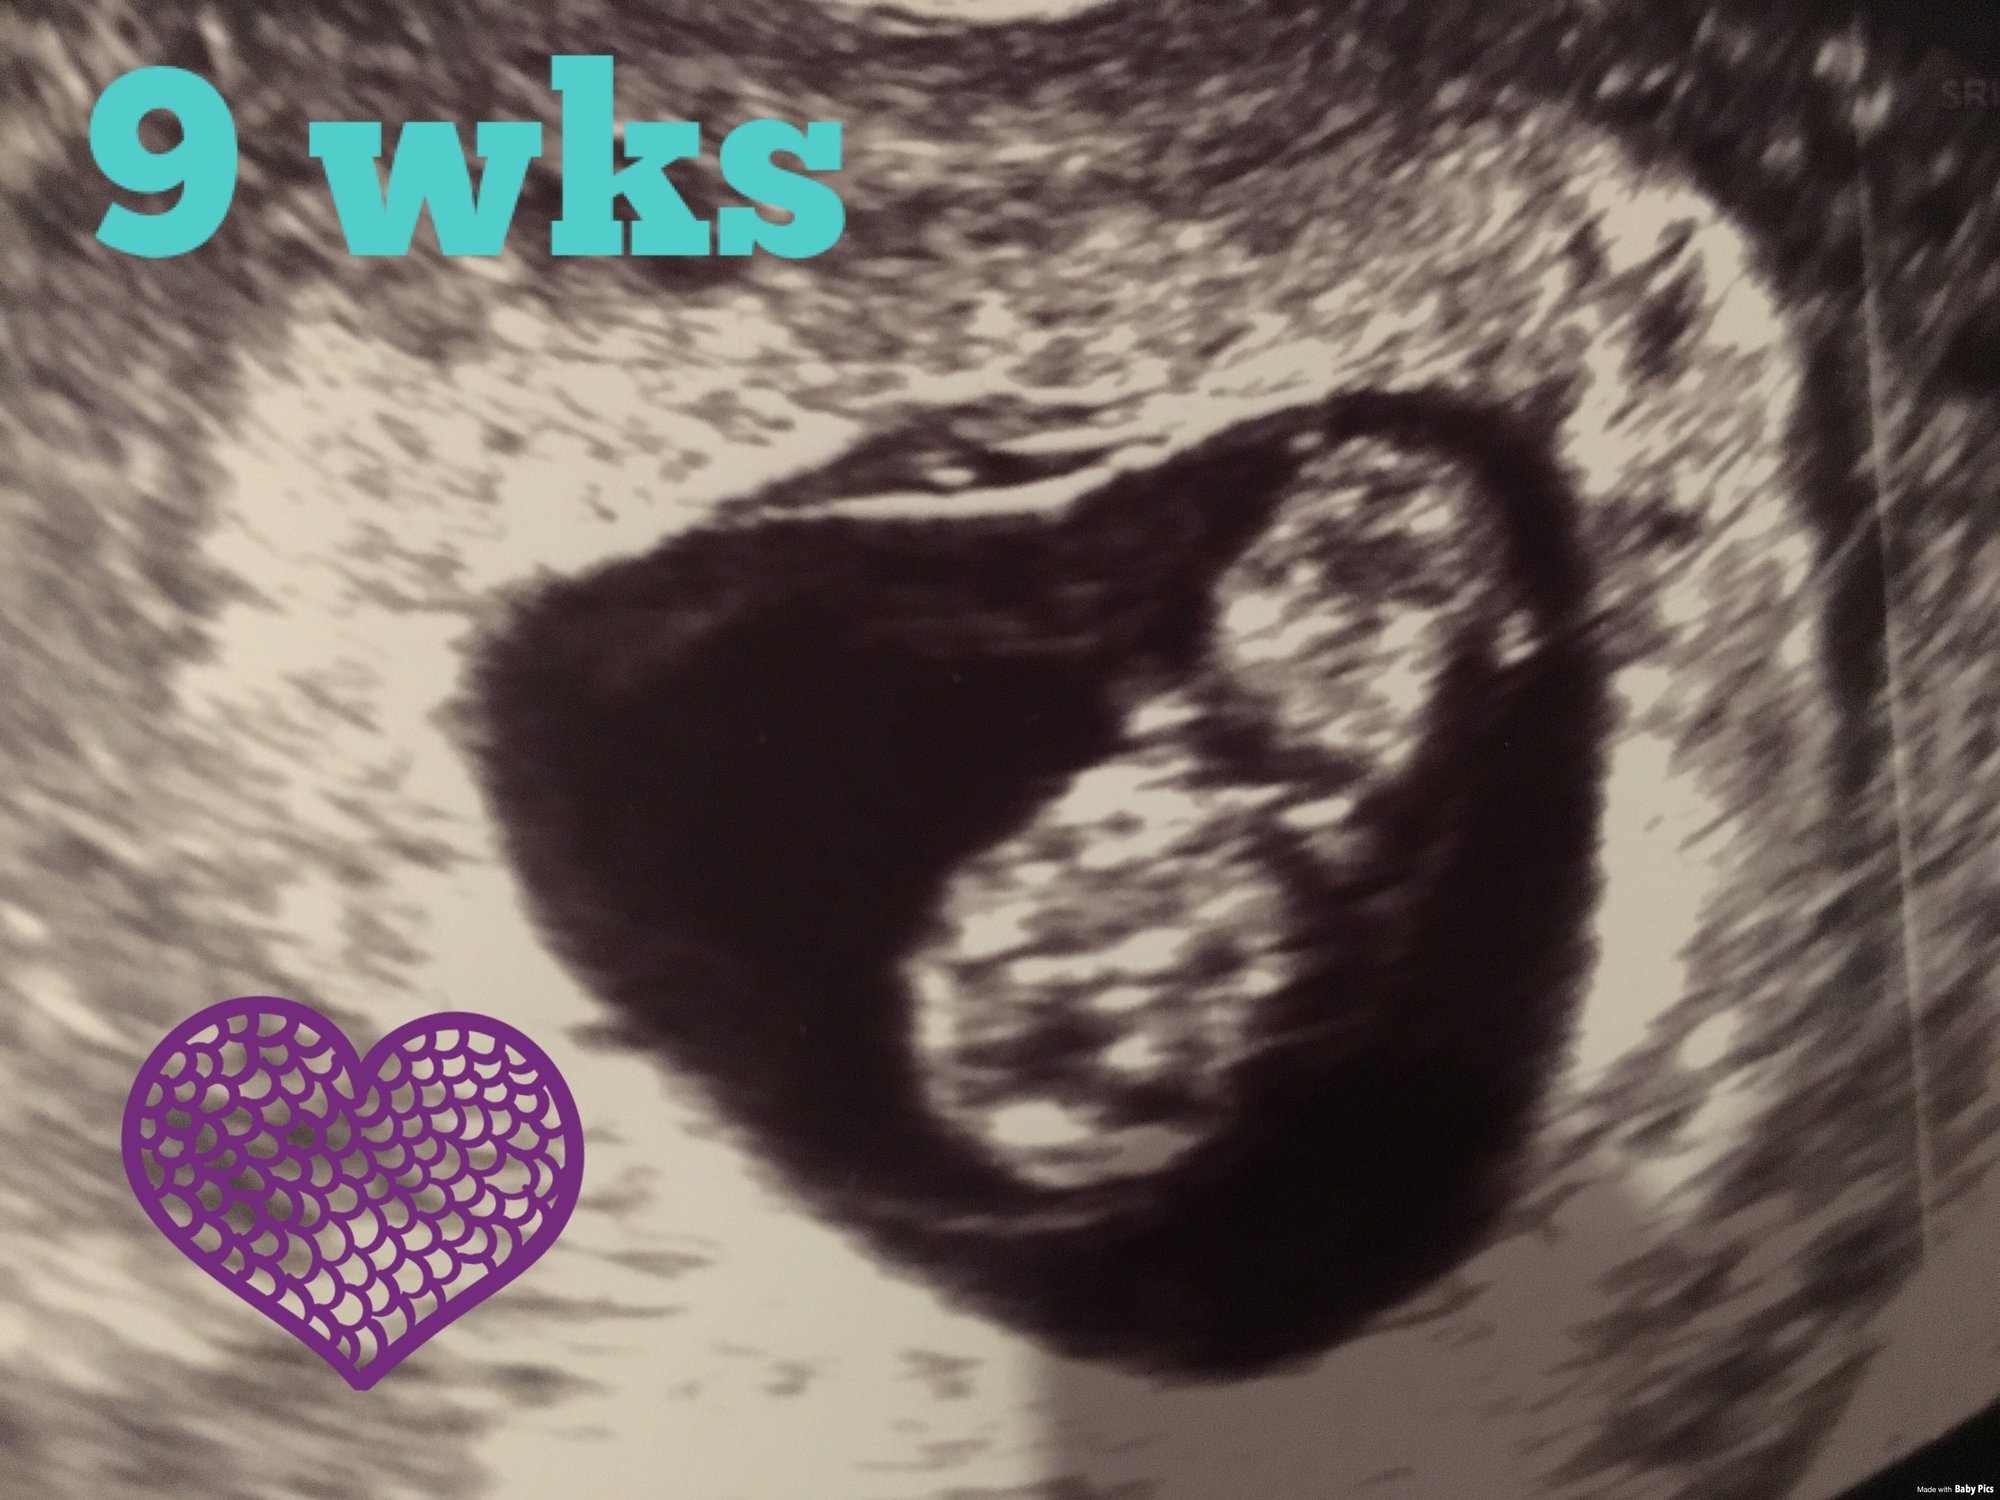

1. How far along are you? 9 weeks, 1 day.

What is your EDD? June 14th.

Just had one yesterday so not another one until Dec. 6th for my 12 week appointment!

4. Anything else you'd like to share? We got to see our little one move yesterday and I've never felt so in love with such a little thing. I already want to show everyone my ultrasound picture (because it's naturally the cutest one I've ever seen, I'm not biased), I can't imagine this will get better as we go lol